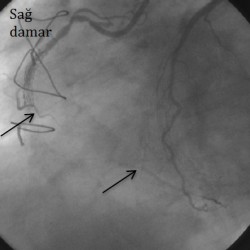

Hastanın sağ damarı tam tıkalı damarları açma yöntemi (cto) ile sol damardan yan kılcal damar

Hastanın sağ damarı tam tıkalı damarları açma yöntemi (cto) ile sol damardan yan kılcal damarlar vasıtasıyla özel mikrokateterler ve teller ile tersten gelinerek açıldı, iki ok arasına stent yerleştirildi.